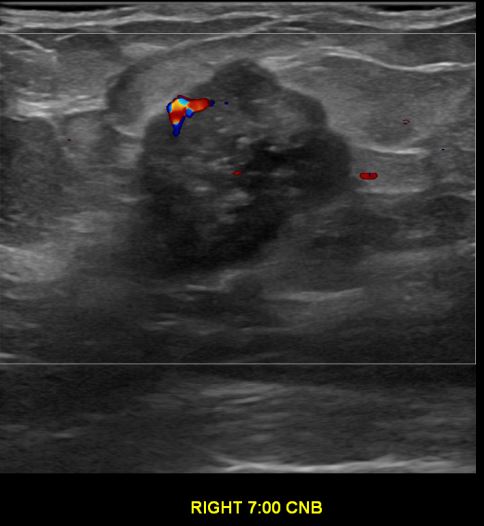

상기환자는 만져지는 멍우리있어  내원하신 50대후반 여성분으로 의심스러운 우측혹 조직검사 시행해 유방암으로 진단되었습니다